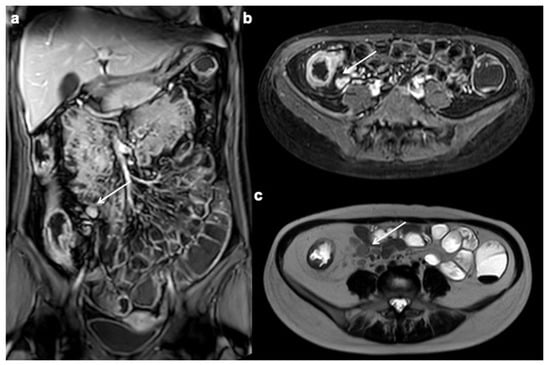

10. Imaging Findings Associated with Active CD Inflammation

Segmental mural hyperenhancement

Wall thickening

| Perienteric edema and/or inflammation |

| Engorged vasa recta |

| Lymphadenopathy |